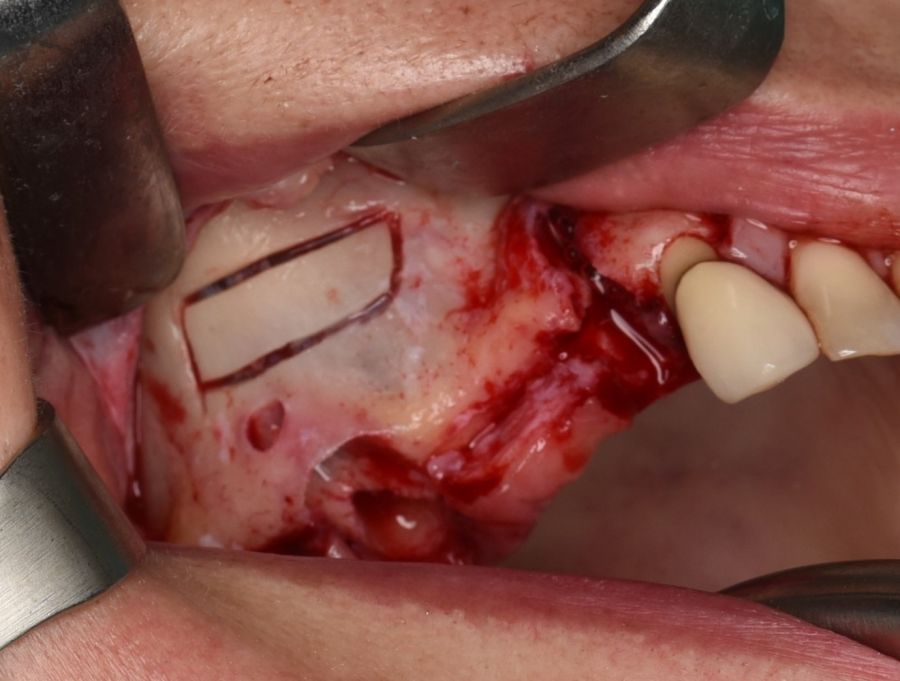

En la historia clínica, no se evidenciaron antecedentes médico-quirúrgicos de interés, alergias medicamentosas conocidas, ni hábitos tóxicos y no presentaba tratamiento médico habitual. Se observó a la exploración intraoral la movilidad de la prótesis fija y caries bajo las coronas con afectación radicular de los pilares 1.4 y 1.7 (Figura 1).

El abordaje quirúrgico del seno se realizó mediante un colgajo a espesor total trapezoidal con una incisión supracretal con descargas verticales vestibulares mesial a 1.3 y distal a 1.7 (Figura 5).